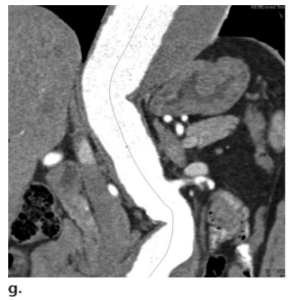

Dấu hiệu động mạch chủ che phủ (draped aorta sign) là một dấu hiệu khác của vỡ động mạch được bao bọc lại (contained rupture), đề cập đến thành sau của động mạch chủ bám sát hoặc “che phủ – draping” dọc theo đường bờ của thân đốt sống kế cận. Động mạch chủ có thể xuất hiện với ranh giới không rõ (indistinct) với thân đốt sống (vertebral body) hoặc cơ thắt lưng (psoas muscle), với tình trạng mất các mặt phẳng của mỡ quanh động mạch chủ. Một lần nữa, hình ảnh tái tạo đa mặt phẳng (MPR) cho thấy một túi phình ra dạng túi (saccular outpouching) chỉ ra tình trạng vỡ khu trú của thành phình động mạch ở vùng có biểu hiện che phủ (draping) trên mặt phẳng axial (Hình 9).

Hình 9. Vỡ phình động mạch được bao bọc lại ở bệnh nhân nam 79 tuổi bị phình động mạch chủ bụng đã biết trước nhưng không có triệu chứng. Hình ảnh CT với MPR mặt phẳng sagittal (a) và axial (b) ban đầu và MPR mặt phẳng sagittal (c) và axial (d) theo dõi thu được bằng thuốc tương phản đường tĩnh mạch cho thấy một túi phình lệch tâm (eccentric outpouching) (mũi tên) của thành sau động mạch chủ làm biến dạng thân đốt sống và tiếp xúc với cơ thắt lưng trái, một dấu hiệu được gọi là dấu hiệu động mạch chủ che phủ (draped aorta sign). Cấu trúc hình túi điển hình của vỡ động mạch được bao bọc lại biểu hiện trên hình ảnh mặt phẳng sagittal theo dõi (c) và có sự tăng lên của tình trạng xuyên thấu từ lòng mạch (luminal penetration) vào vỡ động mạch được bao bọc lại (contained rupture). Bệnh nhân từ chối phẫu thuật.